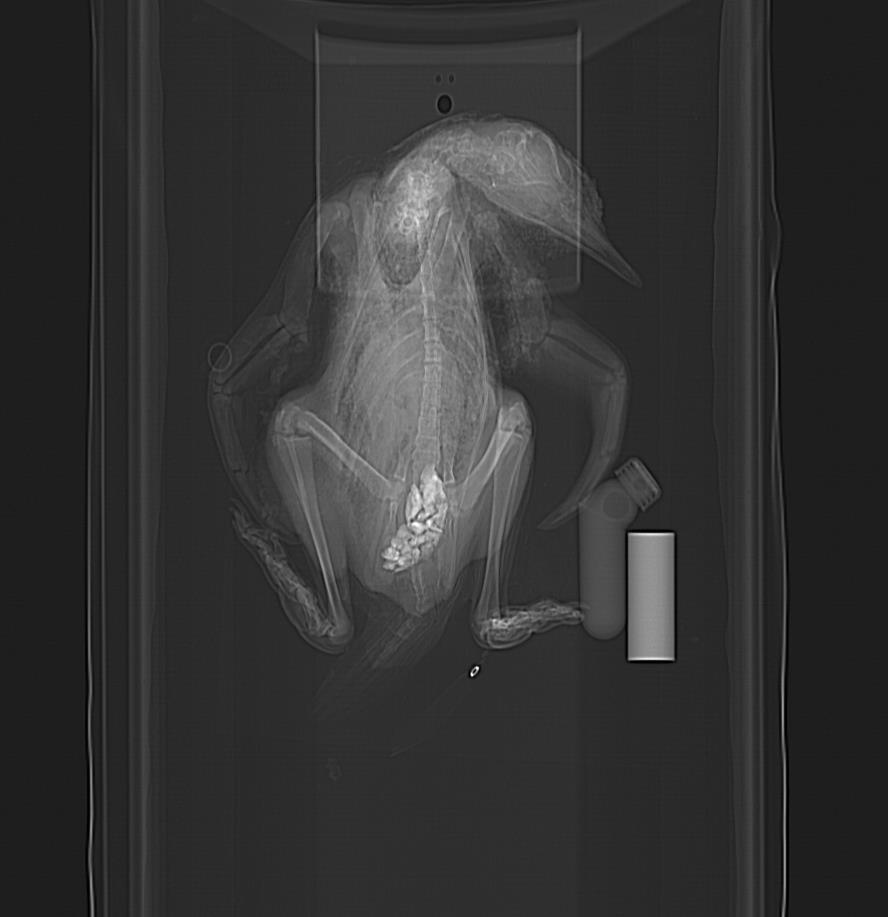

CT reconstruction of adult skeleton. This specimen was gutted and flattened, so the gastroliths are few and scattered. Check out the long tail: